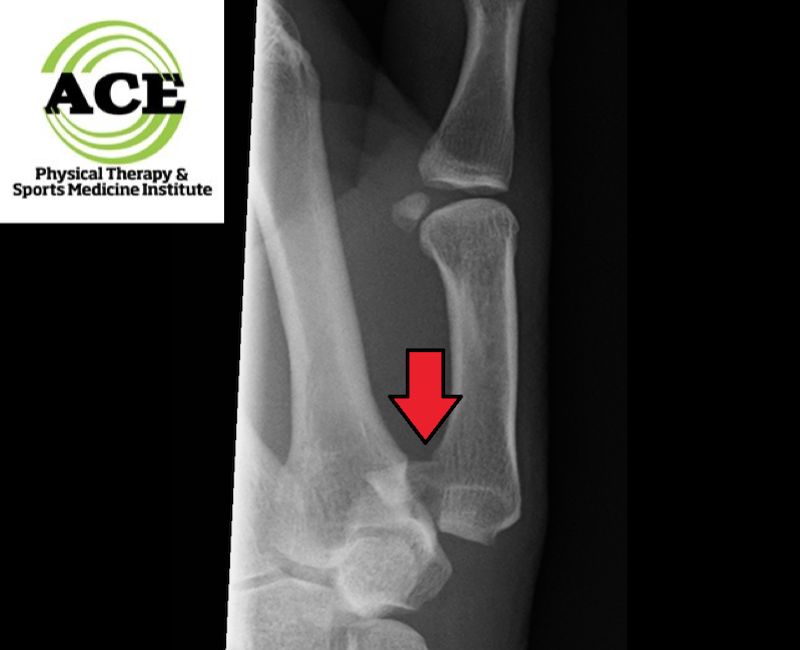

Accurate diagnosis via X-rays is required to establish the proper plan of care.  There are 3 classifications of Bennett fractures.  Type 1 has a single ulnar fragment.   Type 2 is an impact fracture without subluxation of the first metacarpal and finally Type 3 is a combination of an ulnar fragment and metacarpal dislocation.  The severity and type of fracture determine how the patient’s injured thumb is treated by the orthopaedic doctor.

Bennett-Fracture